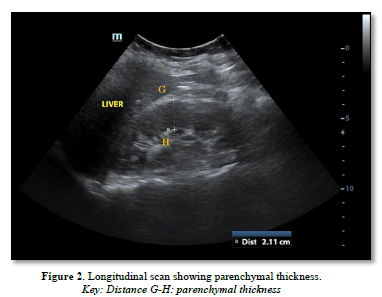

The following parameters were measured (Figures 1 & 2):

Cortical echogenicity: Graded 0-4 vs. liver echogenicity and differentiation.

Renal Cortical Echogenicity Grading [25]

Renal cortical echogenicity was graded on a scale of 0-4 by comparing it to the echogenicity of the liver and medulla, using a standardized grading scale for the liver: Less echogenic than the liver; Equal echogenicity to the liver; Greater echogenicity than the liver with maintained corticomedullary differentiation; Greater echogenicity than the liver with poor corticomedullary differentiation; Greatest echogenicity with loss of corticomedullary differentiation.